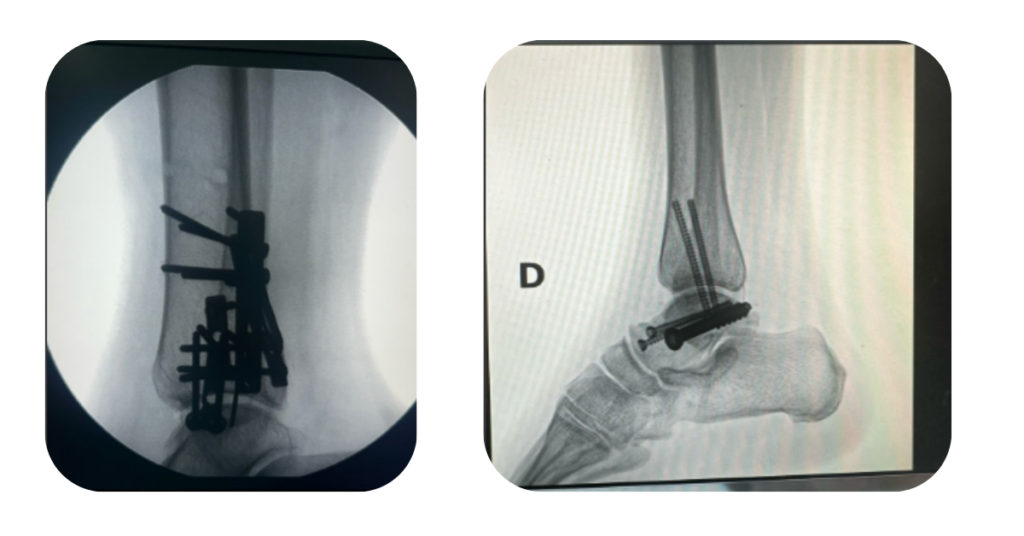

Como é feita a cirurgia do tornozelo?

A cirurgia visa realinhar os ossos quebrados e estabilizá-los com placas, parafusos ou fios metálicos, permitindo que cicatrizem na posição correta. O procedimento é feito com anestesia (geral ou regional) e dura, em média, de 1 a 2 horas.

Em geral:

• O paciente vai para casa no mesmo dia ou no dia seguinte.

• Usa-se bota ou gesso para proteção inicial.

• O apoio do pé operado é evitado nas primeiras semanas (varia conforme o caso).